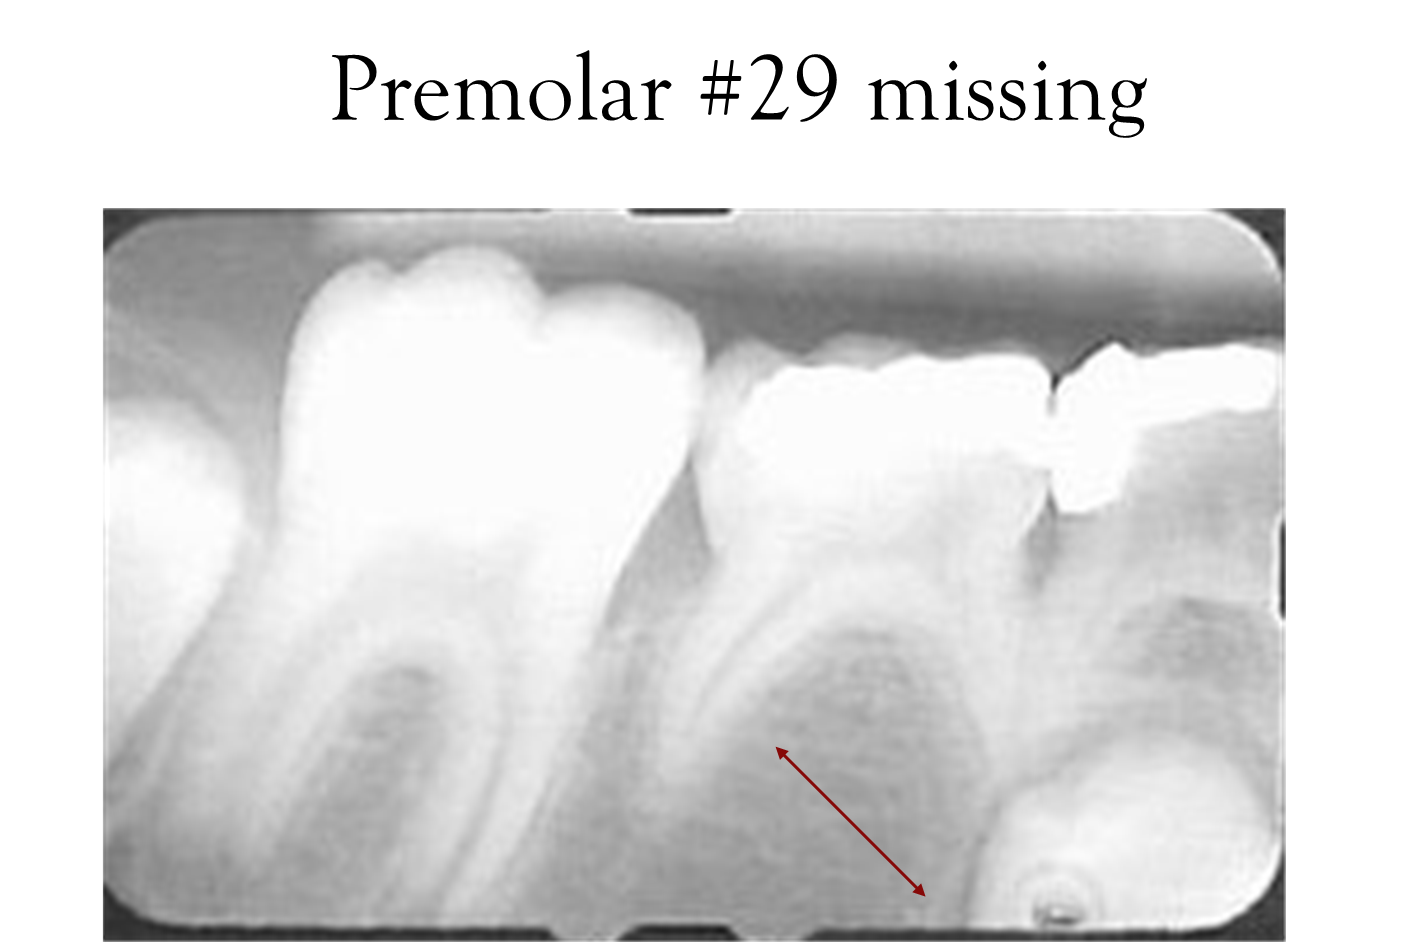

Premolars: Found in the posterior segment, 2 in each quadrant, numbering from 3-5